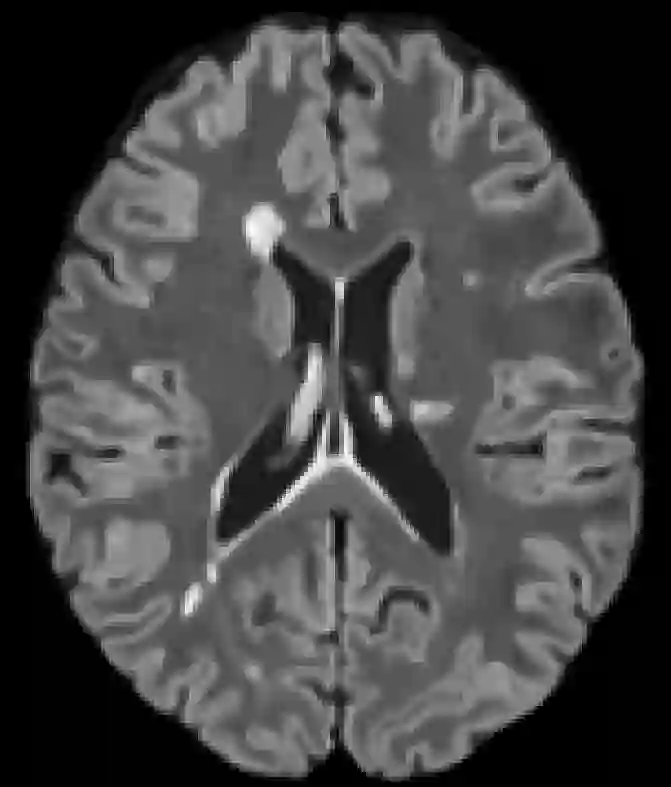

Recently, segmentation methods based on Convolutional Neural Networks (CNNs) showed promising performance in automatic Multiple Sclerosis (MS) lesions segmentation. These techniques have even outperformed human experts in controlled evaluation conditions such as Longitudinal MS Lesion Segmentation Challenge (ISBI Challenge). However state-of-the-art approaches trained to perform well on highly-controlled datasets fail to generalize on clinical data from unseen datasets. Instead of proposing another improvement of the segmentation accuracy, we propose a novel method robust to domain shift and performing well on unseen datasets, called DeepLesionBrain (DLB). This generalization property results from three main contributions. First, DLB is based on a large group of compact 3D CNNs. This spatially distributed strategy ensures a robust prediction despite the risk of generalization failure of some individual networks. Second, DLB includes a new image quality data augmentation to reduce dependency to training data specificity (e.g., acquisition protocol). Finally, to learn a more generalizable representation of MS lesions, we propose a hierarchical specialization learning (HSL). HSL is performed by pre-training a generic network over the whole brain, before using its weights as initialization to locally specialized networks. By this end, DLB learns both generic features extracted at global image level and specific features extracted at local image level. DLB generalization was validated in cross-dataset experiments on MSSEG'16, ISBI challenge, and in-house datasets. During experiments, DLB showed higher segmentation accuracy, better segmentation consistency and greater generalization performance compared to state-of-the-art methods. Therefore, DLB offers a robust framework well-suited for clinical practice.